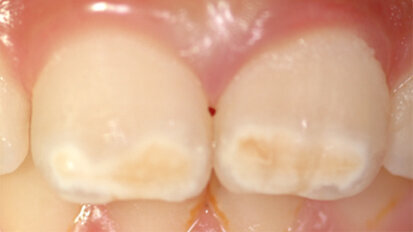

Molárová a incizální hypomineralizace skloviny

Molárová a incizální hypomineralizace skloviny (Molar Incisor Hypomineralisation – MIH) je globální problém postihující každé sedmé dítě. ...